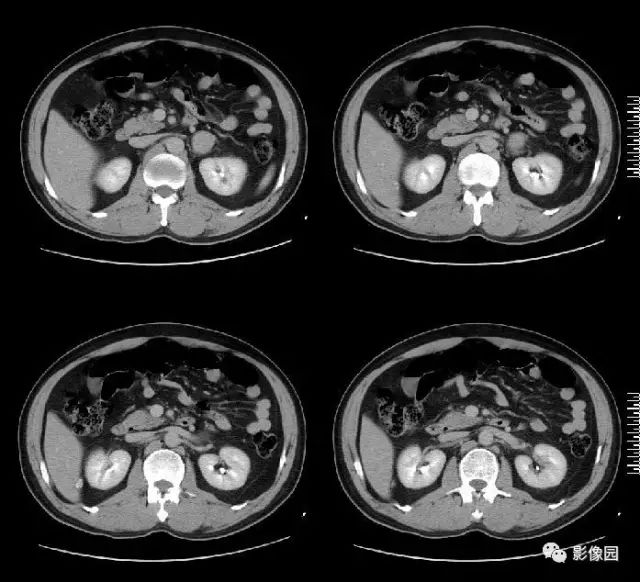

肚肚丫头: 左侧肾上腺见结节状异常密度影,无分叶,边缘光滑,增强扫描呈显著不均匀强化,中心见片状低密度区,考虑:1. 嗜铬细胞瘤;2.腺瘤

【病理结果】左肾上腺嗜铬细胞瘤

影像诊断要点

CT:CT对肿瘤定位可提供较准确信息,诊断准确率高,为常用检查方法。多表现为一侧肾上腺较大圆形或椭圆形肿块,偶为双侧性。直径常为3~5cm,或更大。较小肿瘤密度均一,类似肾脏密度;较大肿瘤常因坏死或陈旧性出血而密度不均,内有单发或多发低密度区,甚至呈囊性表现。少数肿瘤可有高密度钙化灶。增强扫描,肿瘤实体部分明显强化,其内低密度区无强化。